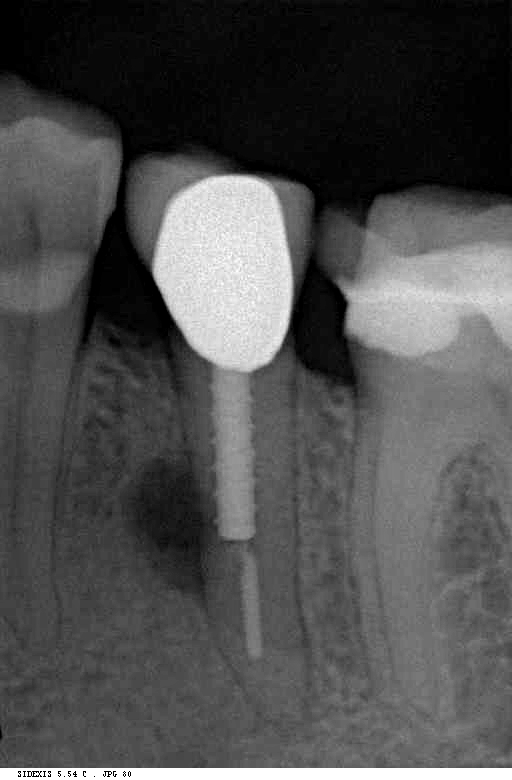

Zähne werden vor der Behandlung klinisch im Mund untersucht und ggf. digital, d.h. strahlungsarm und über Computer, geröntgt. In vielen Fällen bringt die zweidimensionale Röntgenaufnahme nicht genug Erkenntnisse; hier können wir im Bedarfsfall auf unser DVT-Gerät (Digitale Volumentomographie) zurückgreifen, das genaue Diagnostik um ein Vielfaches erleichtert bzw. in manchen Fällen überhaupt erst möglich macht.